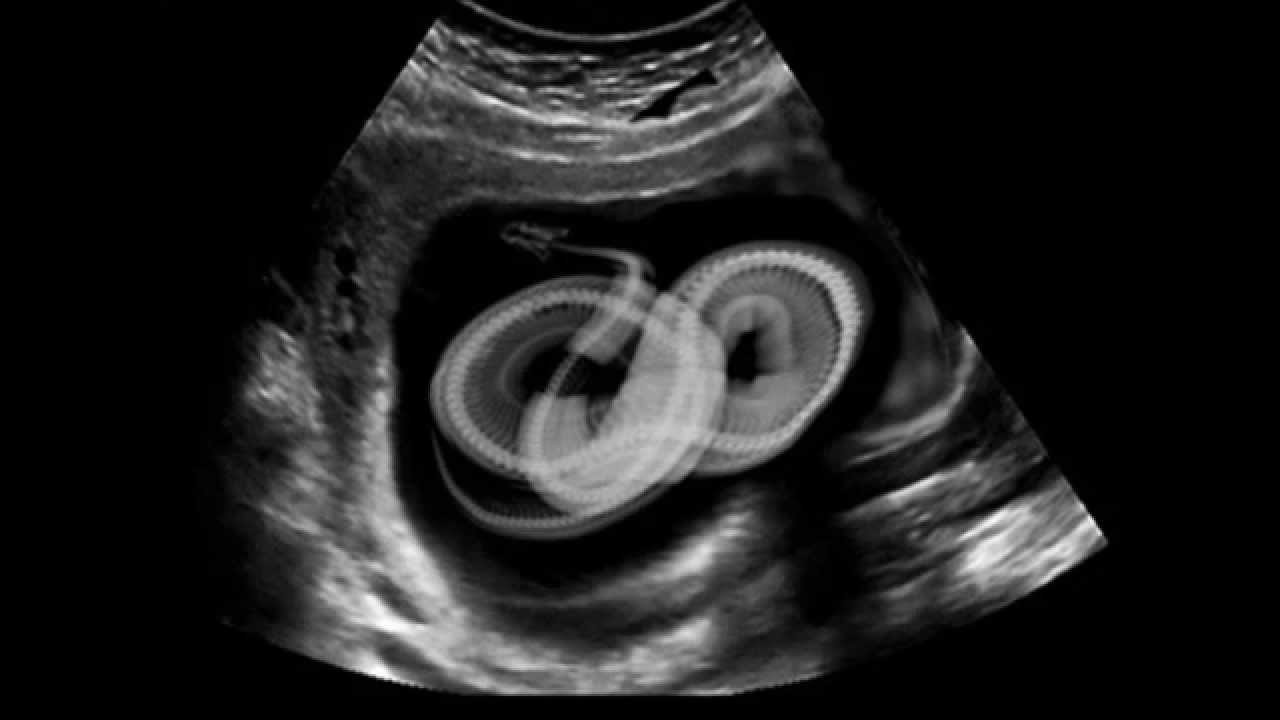

إلا أن الآلام تطورت نحو الأسوأ حتى لم يعد بامكانها احتمالها ، فكان أن أسرع بها زوجها إلى أقرب مستشفى في نيويورك حيث أدخلت قسم الطوارىء على الفور وهي تئن وتبكي من الألم . في المستشفى احتار الأطباء وأربكتهم العوارض التي ألمت بمريضتهم ، خاصةأنها أخذت تتقيأ بقسوة بالغة بعدما انتابتها حالة من الهزات العنيفة . الدكتور ( داميان بيريز ) كان واحداً من الأطباء الذين تواجدوا في غرفةالطوارىء أذهله أمر المريضة إلى أبعد الحدود وخاصة بعد أن خلعوا عنها ثيابها ولاحظوا أن ثمة شيئا يتحرك تحت الجلد في معدتها … الخطوة التالية كانت بأخذ صور أشعة لباتريسيا ، لكن الأطباء لم يصدقوا ما رأوه في الصور…!

وقبل أن يتمكنوا من مناقشة الخطوة التالية التي سيتخذونها توقف قلب باتريسيا عن النبض ولم يكن لديهم الوقت لنقلها إلى غرفة العمليات فأجبروا على اجراء عملية لها فوراً فشقوا لها بطنها ليقع نظرهم على أغرب منظر رأوه في حياتهم … ! و صعق الجميع وأخذوا ينظرون إلى بعضهم بعضاً في ذهول تام غير مصدقين مايرونه أمامهم كانت أفعى بطول 1.83 متر تقبع داخل معدة باتريسيا .